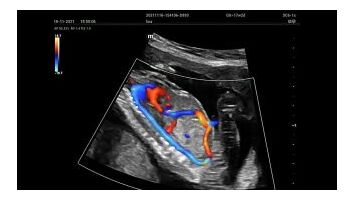

Для эхокардиографии используются секторные фазированные датчики и дополнительные допплеровские режимы с целью исследования сердечной деятельности.